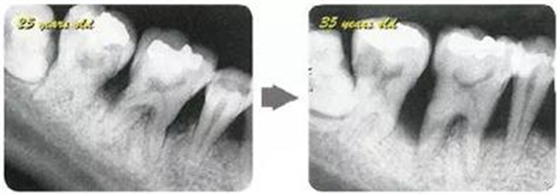

牙周病的發(fā)展因部位不同而發(fā)展程度不同的。10點(diǎn)后的狀態(tài)參考病例①和參考病例②的磨牙處的狀態(tài)相比較,思考下沒(méi)接受治療病情發(fā)展的特別性吧。

參考病例① 35歲女性

在左下第一磨牙在25歲時(shí)近中處可以看到垂直性的骨吸收,但35歲時(shí)吸收停止,原本沒(méi)有見(jiàn)到的遠(yuǎn)中處骨吸收的,現(xiàn)在卻吸收得很嚴(yán)重。

在右下處,原本有大量骨吸收的第一磨牙處的吸收卻變緩慢,原本沒(méi)有吸收的第二前磨牙卻出現(xiàn)了吸收。出現(xiàn)吸收的左上第一磨牙的遠(yuǎn)中處,吸收得越來(lái)越多了。

把10年間的變化做成表格。牙周病的發(fā)展根據(jù)各個(gè)人會(huì)不同,即使通一個(gè)人,不同牙齒,不同牙面發(fā)展的狀態(tài)也不同。